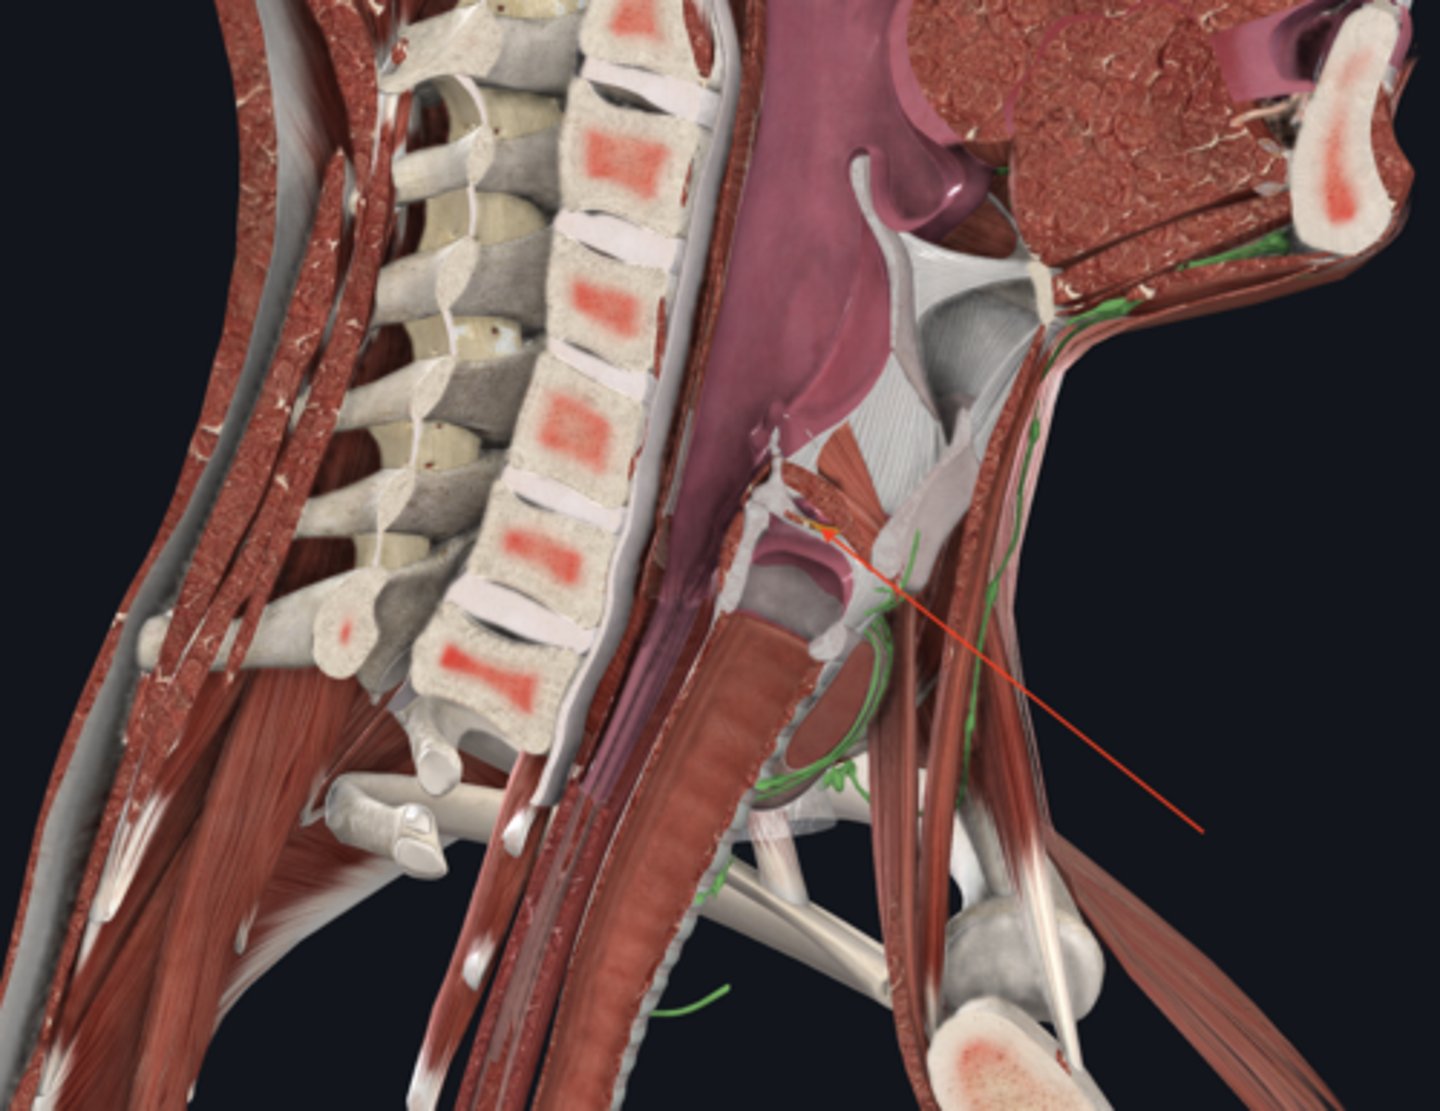

larynx

name the green portion

hyoid bone

name the green portion

thyroid cartilage

name the green portion

cricoid cartilage

name the green portion

arytenoid cartilage

name this cartilage

vocal ligament

name the ligament in this area

vocalis muscle

name this muscle

trachea

tracheal cartilages

annular ligament

right main bronchus

left main bronchus

anterior scalene

middle scalene

posterior scalene

sternocleidomastoid

intercostal muscles

pleural sac

serous membrane that surrounds the lungs and has a visceral and parietal layer

scalene muscles (surface anatomy)

name these muscles

thyroid cartilage (surface anatomy)

Adam's apple

trachea (surface anatomy)

feel for trachial cartilages